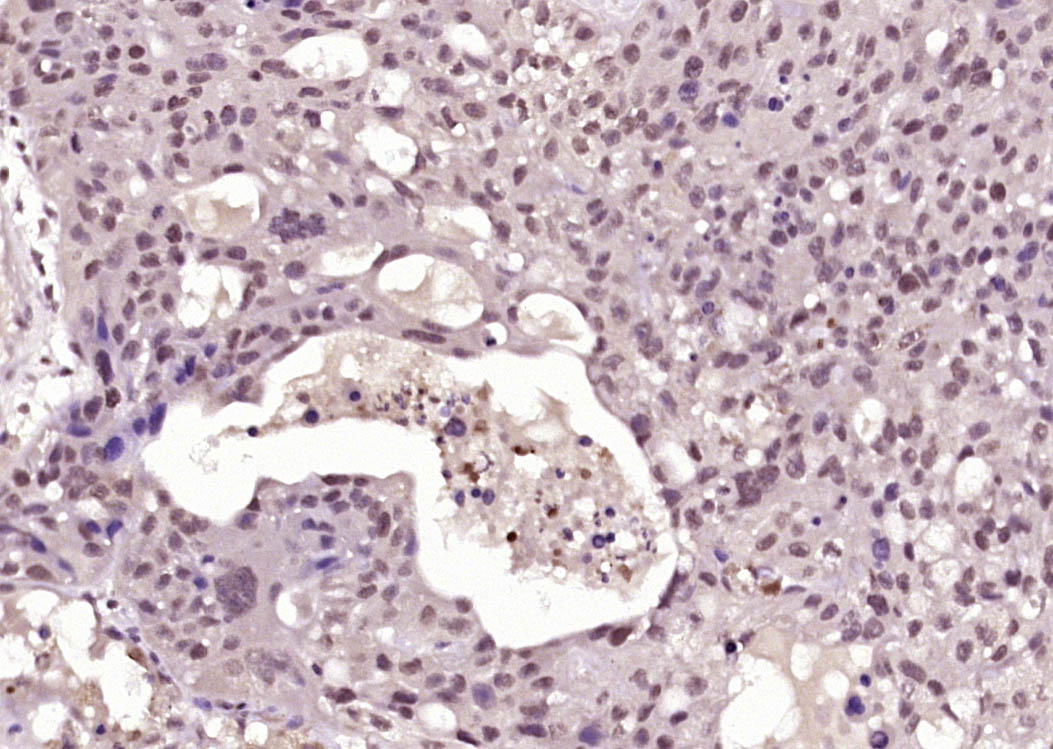

Paraformaldehyde-fixed, paraffin embedded (Human skin carcinoma); Antigen retrieval by boiling in sodium citrate buffer (pH6.0) for 15min; Block endogenous peroxidase by 3% hydrogen peroxide for 20 minutes; Blocking buffer (normal goat serum) at 37°C for 30min; Antibody incubation with (Phospho-BRCA1 (Ser1423)) Polyclonal Antibody, Unconjugated (bs-5222R) at 1:400 overnight at 4°C, followed by operating according to SP Kit(Rabbit) (sp-0023) instructionsand DAB staining.